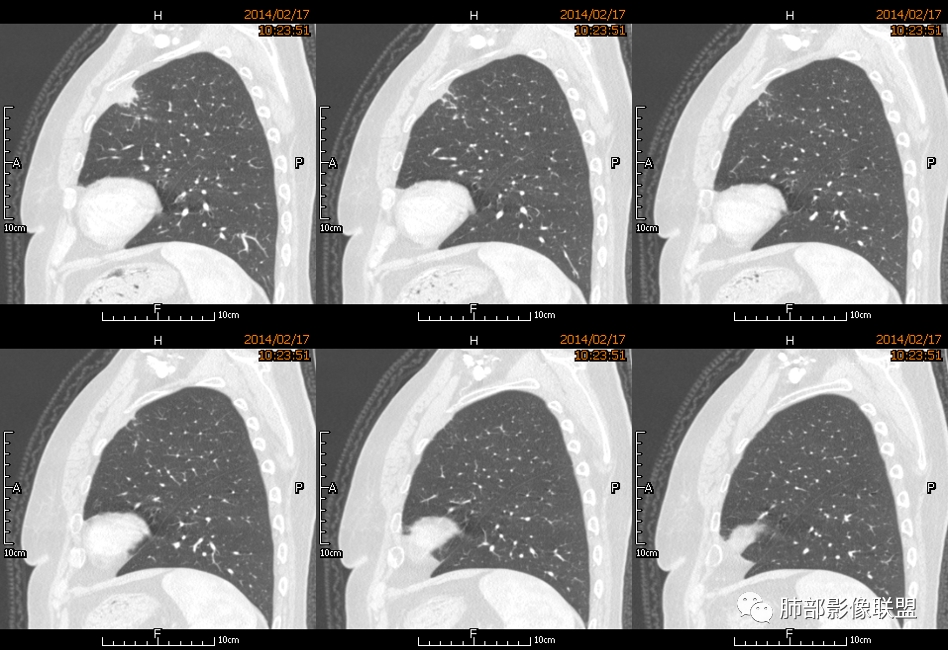

薏米: 老年女性,急性起病,咳嗽,咳痰,咯血,白细胞低,胸部CT提示左肺上叶可见一团块样密度增高影,边缘平直,部分略有膨隆,内可见支气管进入后截断,小的空洞,血管造影,坏死,明显强化,周边可见少许索条,考虑炎性病变,肺脓肿可能。鉴别结核,隐球菌。

一切∮随缘: 定位:肺内,左肺上叶肿块,呈长条状,平行血管束生长,边缘分叶,平扫密度均匀,增强后不均匀强化,可见低密度坏死,近段支气管及血管穿行病灶内,远端堵塞支气管,血管似有破坏,周围散在点状小结节,及纤维索条影,考虑恶性:腺癌,类癌,淋巴瘤。鉴别结核及隐球菌。

红星: 老年女性,咳嗽咳痰10天,痰中带血4天。左肺上叶前段胸膜下肿块影,沿支气管方向走行以膨胀生长为主,局部有收缩改变,支气管血管绝断,中间有小片状的坏死及小的空洞影,增强扫描病灶明显的强化,病灶周围网格状的小叶间隔增厚。拟左肺上叶前段浸润型腺癌并癌性淋巴管炎。鉴别诊断结核肉芽肿。

秦化君: 左肺上叶前段胸膜下软组织密度肿块影,边缘清晰,部分边缘膨隆,纵隔缘弧形内凹,脂肪界面清晰。肿块中心密度减低,支气管进入病灶后截断,似有扩张表现,病灶周围可见小叶间隔增厚,斑片影,近端支气管似管壁增厚。增强后明显强化,中心见低密度区。考虑:1.肉芽肿性炎?2.IMT?3.淋巴瘤?

傅昌瑜: 老年女性,咳嗽咳痰10天,痰中带血4天。左肺上叶前段胸膜下肿块影,沿支气管方向走行,膨胀生长为主,局部边缘似有收缩改变,中间有小片状的坏死,支气管进入,增强扫描病灶明显的强化,血管走形较自然(血管漂浮征?),病灶周围网格状的小叶间隔增厚。考虑淋巴瘤可能性大,注意鉴别炎性肉芽肿及肺腺癌。

水晶石头: 患者老年女性,咳嗽咳痰10天,痰中带血4天余。查血常规白细胞低;肿瘤标志物、凝血功能正常;血生化:蛋白低;C反应蛋白、血沉稍升高。胸部CT:左肺上叶前段胸膜下沿气管支气管走形肿块影,长轴与胸膜平行,见分叶、毛刺、支气管截断、空泡征象。增强明显强化,且见血管造影征及病灶内小灶低密度坏死区。左肺上叶尖后段见一结节灶。综合考虑恶性病变可能大,腺癌或淋巴瘤可能。鉴别诊断肺脓肿。

尘缘: 老年女性,咳嗽咳痰10天,痰中带血4天,白细胞及中性粒明显减低,轻度贫血。影像表现:左上叶肿块,边缘膨隆,局部平直,支气管稍扩张,进入后远端堵塞,内见小空洞及不规则坏死区,增强后强化明显,坏死边界较清,并见环状强化区,内部血管走行自然,周围见小叶间隔增厚呈大网格征。初步诊断:慢性炎性伴脓肿形成及肉芽组织增生。鉴别淋巴瘤及腺癌,先抗炎治疗后复查或直接穿刺明确。

张延军: 左肺上叶前段软组织影,偏下缘见充气支气管,部分支气管壁与肿块近端增厚狭窄。实性部分见血管穿行,边缘平直并局限性凹陷,增强扫描内见斑片状低密度区,界不清,实性部分中度强化,病变外宽内窄,基底贴于胸壁,周围肺组织内见条片状密度增高影,考虑炎性,结核?腺癌待排。

毛勤香: 老年女性,左肺上叶胸膜下肿块,部分膨隆部分收缩,边缘毛糙模糊,周围少许索片状影,小叶间隔增粗,支气管进入后截断,增强扫描明显不均匀强化,内低密度区无明显强化,血管走行尚可,首先考虑感染性变并脓肿形成,鉴别淋巴瘤,建议抗炎后复查。

宇宙星空: 外大内小,近端支气管壁增厚,爬树征,内部坏死不均匀,都比较典型了。支持结核,鉴别炎性肉芽肿、慢性脓肿。

王崇军: 老年女性,咳嗽咳痰10天,痰中带血4天。左肺上叶前段胸膜下 肿块影及段形态密度增高影,沿支气管方向走行,膨胀生长为主,局部有收缩改变,支气管进入并闭塞,中间有小片状的坏死及小的空洞影,空洞漂浮在坏死边缘,增强扫描病灶明显的强化,坏死边界清楚,似乎有轻度强化环,病灶周围网格状的小叶间隔增厚及小结节影,外侧胸膜呈糊墙改变。考虑为肺脓肿,这么大的病灶,竟然没有发烧,白细胞低,CPR轻度升高,均与脓肿不符,所以恶性待排,短期抗炎治疗后复查,病灶没有变化,脓肿就可以排除,恶性基本可以确定。

空格: 临床特点:老年女,血糖略高,低蛋白血症,白细胞低,提示有免疫下降的存在。机会性感染存在机会。黄浓痰一般常见于炎性病变,痰中带血则肿瘤多见,两厢pk,觉得黄脓痰胜,除非肿瘤继发感染一般不会黄脓痰。影像:一 、良性征像:1.病灶整体是个尖端指向肺门的三角形病灶;2.胸膜平直,胸膜外少量液体糊墙;3.支气管未见明显截断,内壁毛糙?4.近端支气管弥漫性增厚,结核脓痰咯出,看做引流支气管;5.多个层面病灶呈直边征,多角征,无明显分叶;6.病灶内坏死边缘光整,伴小气泡。小叶间隔增厚光滑锐利,无结节,不太像癌淋。二、恶性征像:部分层面向胸膜外突,略有占位效应。总体考虑感染性病灶,霉菌可能。结核抗体阴性,可以排除?

刘和林: 老年女性,咳嗽咳痰10天,痰中带血4天。左肺上叶前段胸膜下 肿块影,沿支气管方向走行,膨胀生长为主,局部边缘似有收缩改变,中间有小片状的坏死,坏死区内见小气泡,支气管进入、部分填充、部分末端稍显扩张,增强扫描病灶明显的强化,周围肺不干净,其上肺见小叶间隔增厚。肺癌、淋巴瘤、炎性肉芽肿?肺癌:支气管末端稍扩张,周围类似树芽征改变,不太符合。淋巴瘤:数个小气泡,明显强化,周围树芽征样改变,不太符合。

王武章: 灶内低密度,花环样强化,血管穿行漂浮,邻近胸膜并未广泛增厚也未牵拉但接触面脂肪密度略高且模糊。考虑IMT,鉴别慢性炎症相关的非特异性瘤样病变。